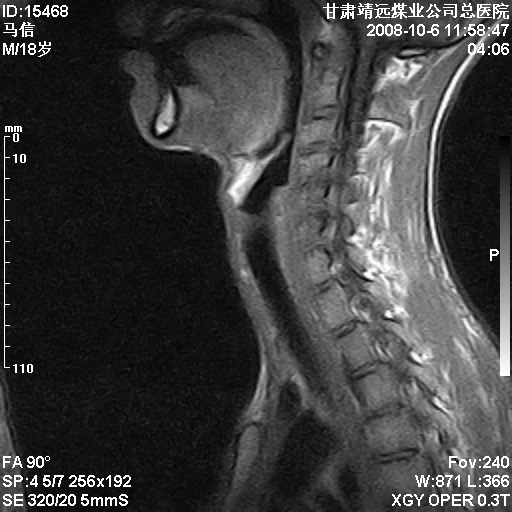

腰椎的改变是不是正常发育的改变,还是打篮球的长期慢性损伤。

考虑 c3-4 c4-5 c5-6椎间盘突出,l3-4 l4-5 l5-s1椎间盘变性

后纵韧带增厚,颈2/3、3/4、4/5、5/6椎间盘变性、突出;椎体有旋转,提示椎小关节有问题;腰椎间盘变性,许莫氏结节。

后纵韧带增厚,颈2/3、3/4、4/5、5/6椎间盘变性、突出;椎体有旋转,提示椎小关节有问题。腰椎诸椎体终板骨骺炎可能性大!支持!

椎体终板骨骺炎可能性大!支持!